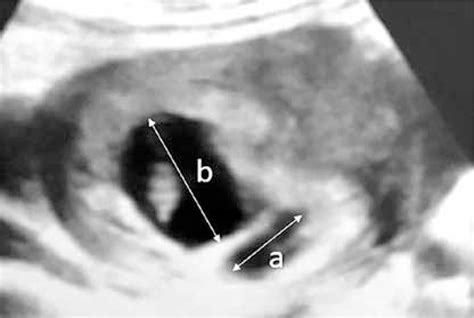

• Transvaginal Ultrasound: This is the gold standard for diagnosing a subchorionic hematoma. The imaging allows the doctor to visualize the size and location of the blood clot relative to the gestational sac.

• subchorionic hematoma pregnancy pictures